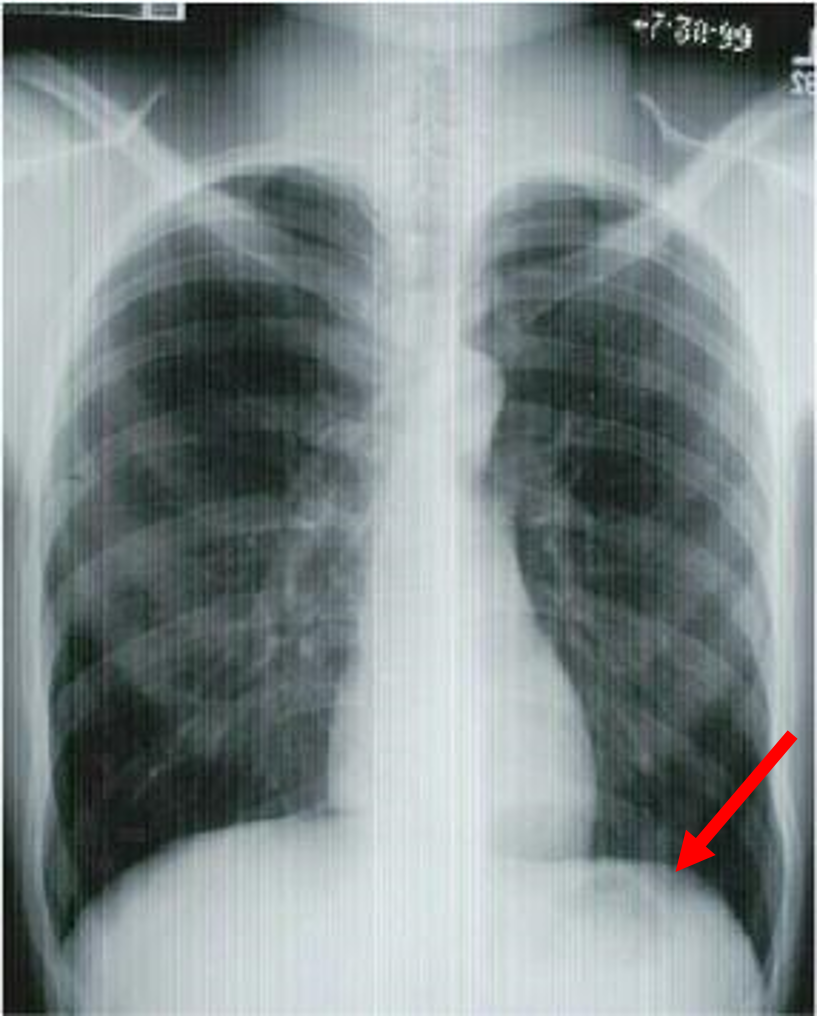

what is this? when would you take this?

expiratory AP

looking for pneumothorax